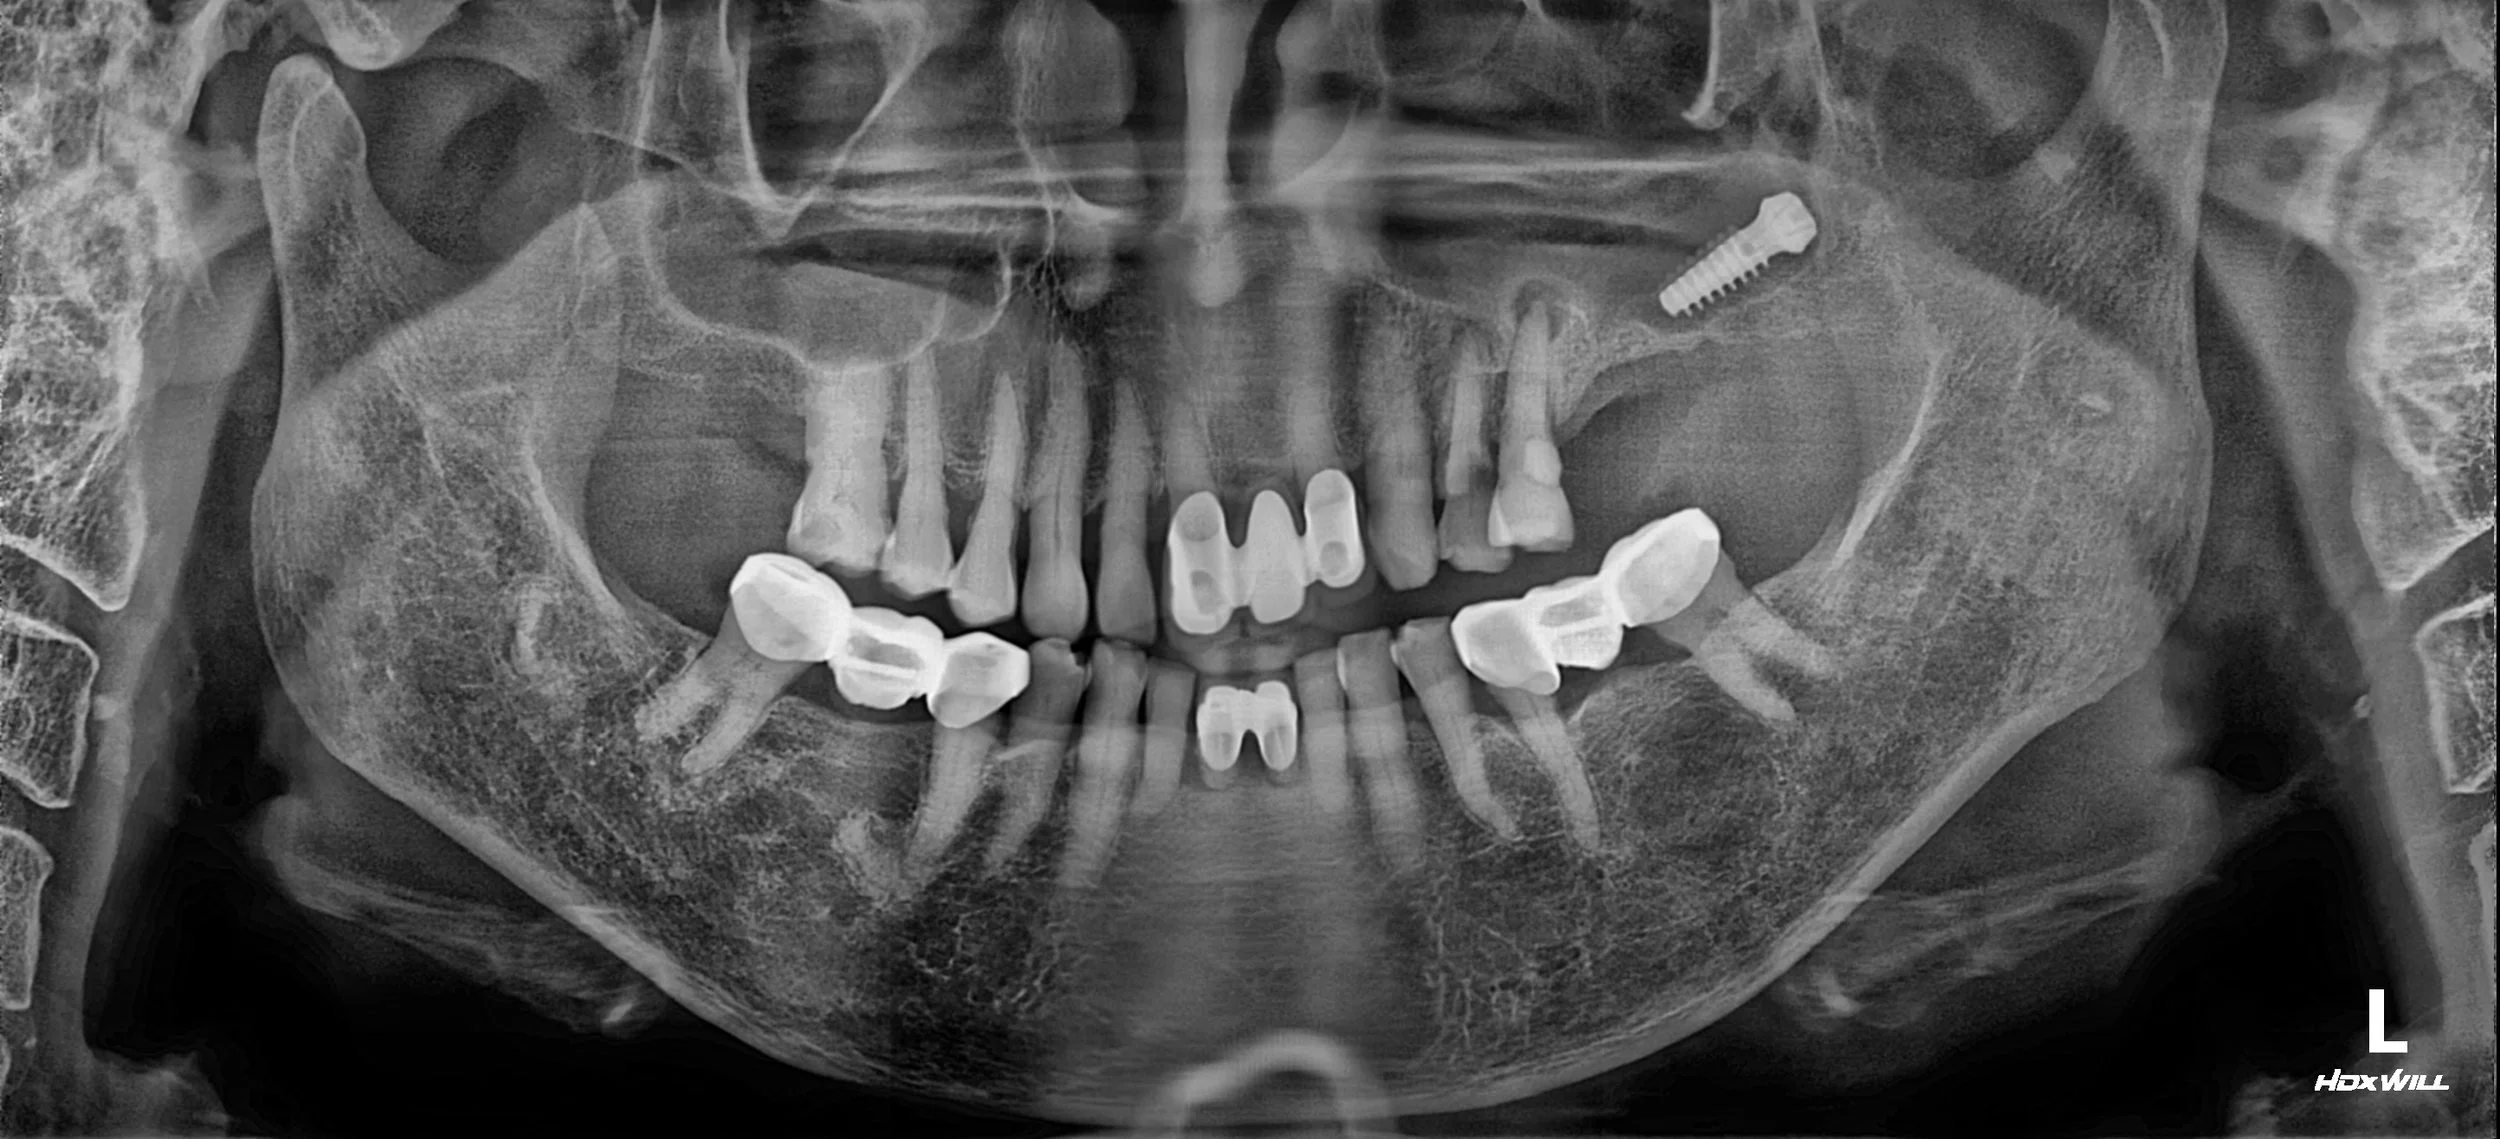

Reversing the effects of generalized rampant caries and occlusal collapse in a female patient in her 20s. A tooth-preserving, implant-assisted approach focused on stable VDO elevation and overcoming social anxiety.